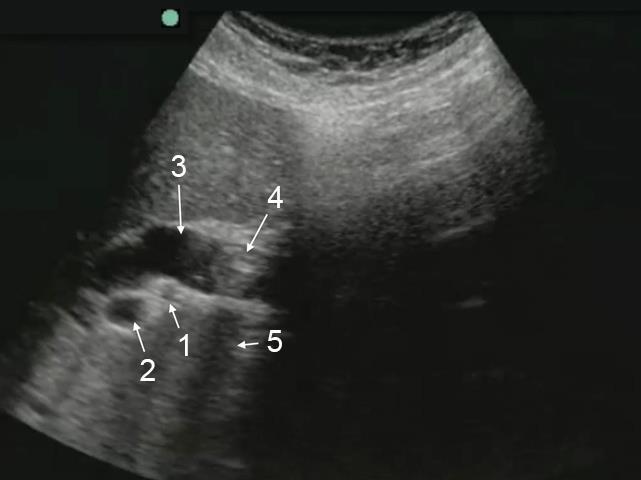

Gallbladder Obstructed Common Bile Duct (CBD) Anatomy Image

1. Hepatic Artery

2. Main Portal Vein (PV)

3. Common Bile Duct (CBD)

4. Common Bile Duct Stone

5. Shadow from Stone